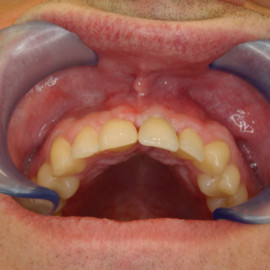

Brakujących pięć zębów dolnych w odcinku wargowym. Rekonstrukcja tkanek i rehabilitacja protetyczna.